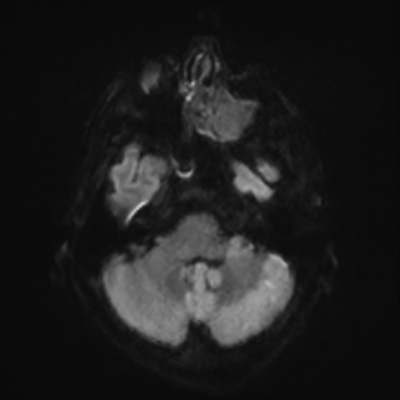

MRI brain (DWI)

You can clearly see diffuse cortical and basal ganglia diffusion restriction, and that of his deep cerebellar nuclei as well. The right occipital lobe abnormalities are a little more prominent, but then you remember that he is known to have had a right occipital stroke weeks ago.